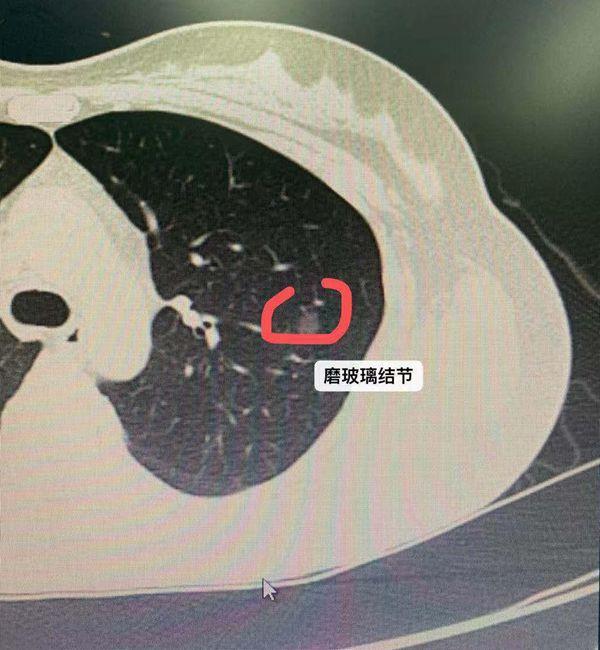

结节密度也是非常重要的一个判断标准,比如说边缘光滑的毛玻璃样改变,常常是肺癌的早期状态。而一旦磨玻璃样结节中的实性成分,也就是密度高的成分越多,这个结节恶性的可能性就越大。

第二,就是结节的形态。比如说成分叶状生长的结节,有毛刺的,边缘不光滑的,厚壁空洞的,有血管生长入内的,都是恶性的表现。此外,判断结节是否为恶性还要观察它的生长速度,良性的结节生长较为缓慢,或者呈爆发性快速生长,而恶性的结节一般生长较为快速。以上这些都是影像学的判断依据,但是这样判断并不准确,只是一个可能性,真正确诊还需要组织病理学的检查。